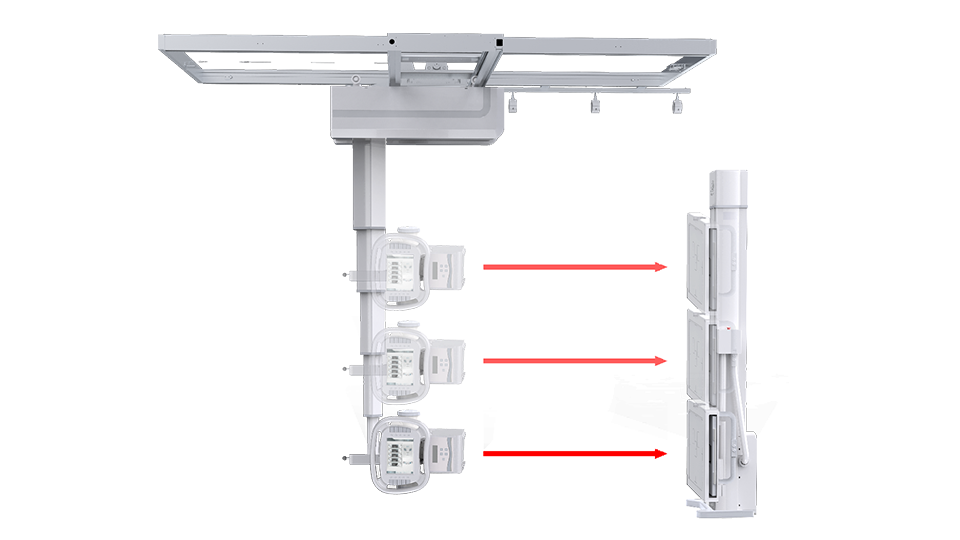

● 自動對中

球管自動對準探測器中心點,保證畫面成像視野準確,無需醫生手動校準。

● 自動跟蹤

配備球管與平板聯動控制系統,平板端上下移動時,球管端自動跟蹤。